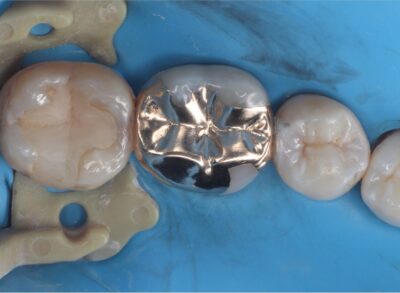

• 銀歯を白くしたい

虫歯の最終形態、難治性根尖性歯周炎から歯を救う「歯根端切除術」や、グラグラの重度歯周病を改善する「歯周組織再生治療」など、世界基準の先進医療を日々実践しています。